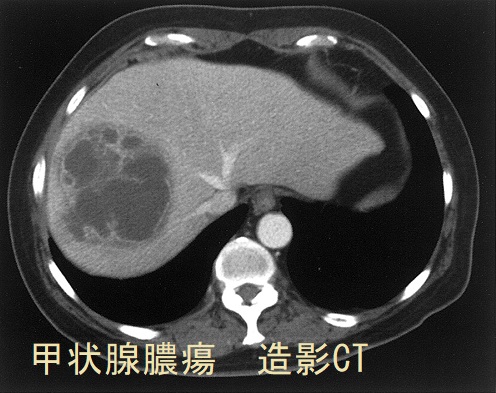

クレブシエラ甲状腺膿瘍 造影CT画像;リング状増強がくっきり。甲状腺膿瘍は甲状腺超音波(エコー)検査より造影CT検査の方が有用かもしれません。[Clin Mol Hepatol. 2018 Mar;24(1):88-91]

糖尿病やその他の免疫不全の無い健康な55歳の女性が、クレブシエラ・ニューモニエ(Klebsiella pneumoniae)による肝膿瘍、甲状腺膿瘍と化膿性内眼球炎(内因性眼内炎)を起こした報告があります。[Clin Mol Hepatol. 2018 Mar;24(1):88-91]。